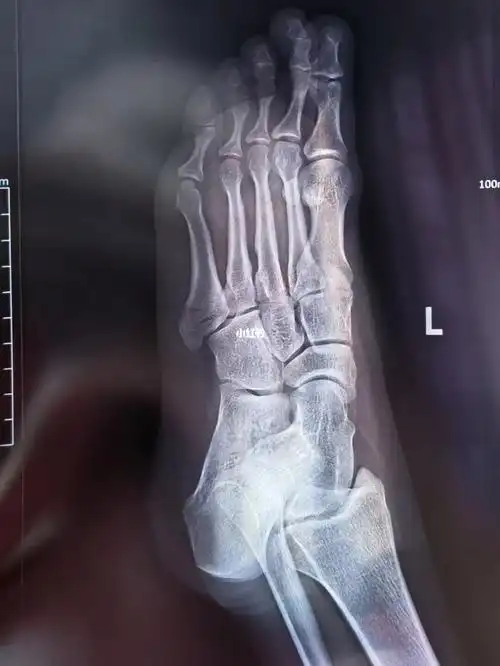

跖骨多发骨折(霸州市中医院骨科李艳阳团队)~创伤篇

第5跖骨基地部破裂骨折第一天